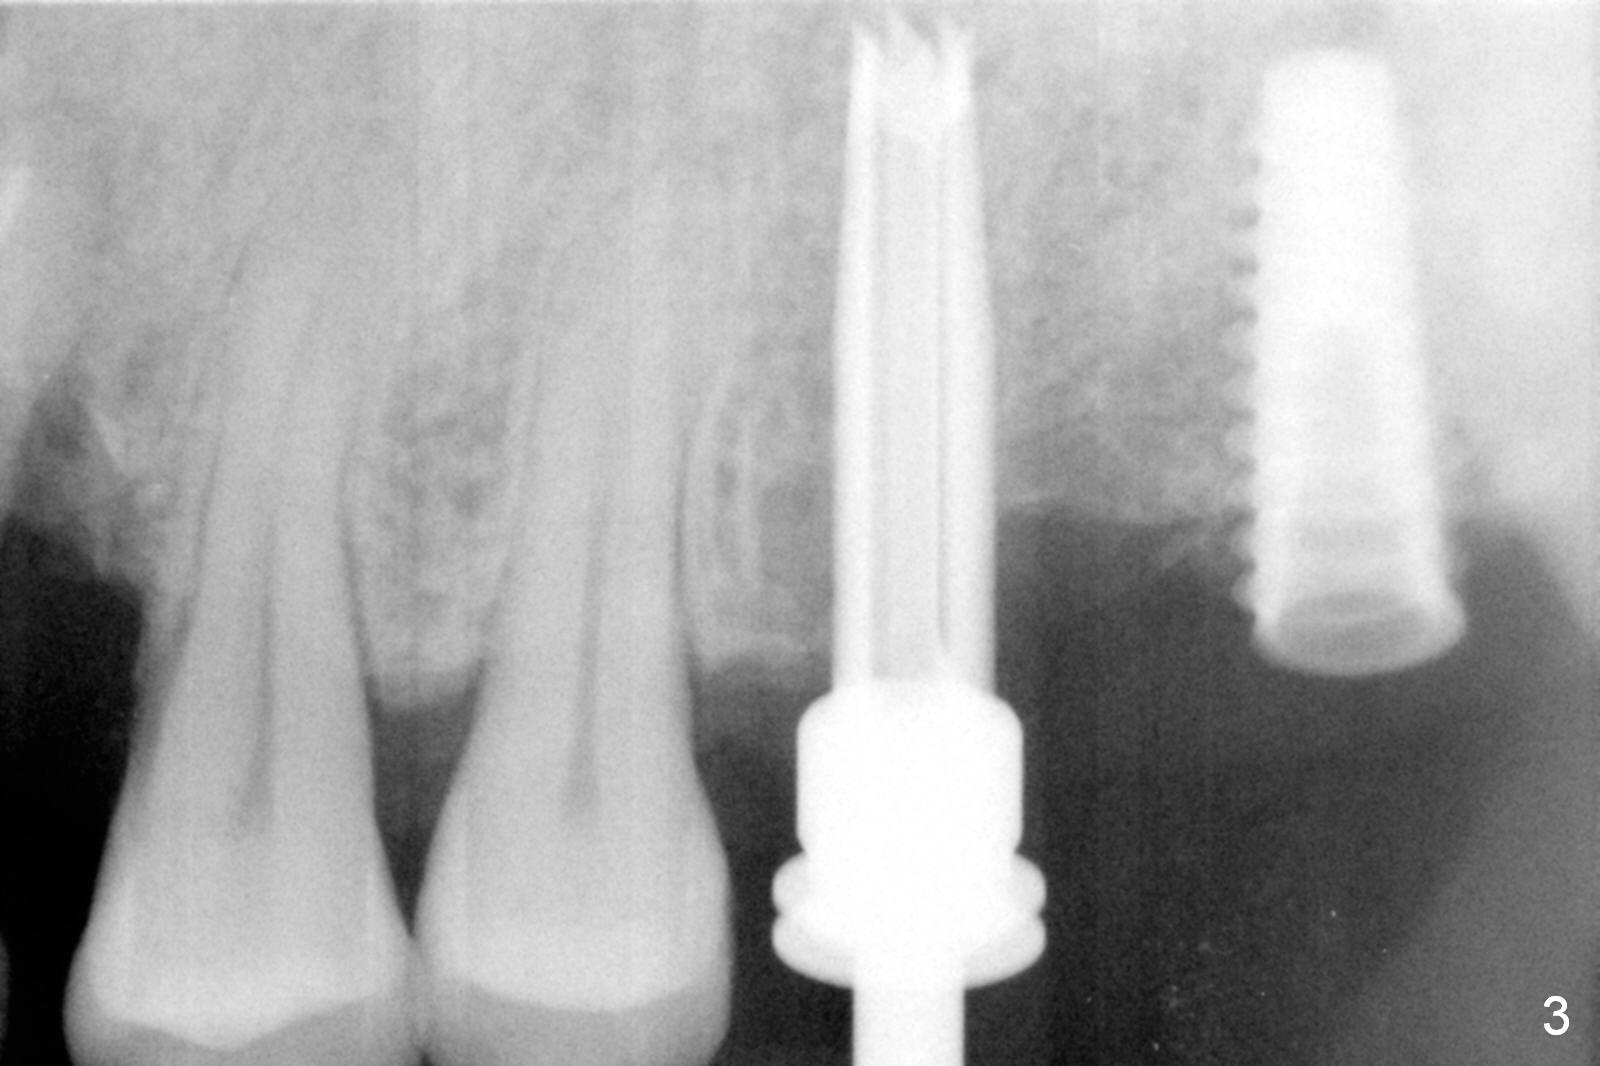

As shown by CT, the ridge at #14 is narrower than that of #15 (confirmed after incision), whereas the density at #14 is higher than that of #15. The osteotomies are established by combination of magic osteotomes and drills after change in trajectory (Fig.1-3). Following placement of 4.5x13 and 5x13 mm IBS implants and 6x4(3) and 6.5x4(3) mm pair abutments at #14 and 15 (Fig.4), flaps are sutured for hemostasis. Since the patient does not tolerate the surgery too well (unstable hypertension and oozing), immediate provisional is delayed. Periodontal dressing is applied instead. While the implants are healing, porcelain chips at the upper anterior bridge. There appears no bone resorption 6 months postop (Fig.5). Impression is taken following changing abutment to 5x4(2) mm at #14 and Diode gingivectomy. A panoramic film is taken 1 year 2 months post cementation. CT taken 2 years post cementation shows relatively good trajectory of these 2 implants (Fig.6,7).